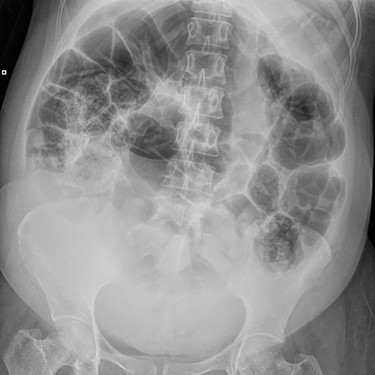

On examination, she was in marked discomfort with a grossly distended abdomen. Despite generalized voluntary guarding, her abdomen was soft, with no focal peritonism. Bowel sounds were frequent and high-pitched, and percussion was tympanic throughout the upper abdomen. Abdominal X-ray by the treating Obstetrics team noted dilatation of the entire bowel above the pelvic brim, as shown in Fig. 1. Blood results were unremarkable, with Hb 113, WCC 17.9, CRP 64, K 4.1, Mg 0.81, and normal renal and liver function. A computed tomography (CT) abdomen and pelvis was organized to rule out mechanical obstruction.

X-ray Abdomen, 24 h after commencement of symptoms. Widespread dilatation of large and small intestines stopping at the level of the pelvic brim. Moderate faecal loading in the caecum and descending colon.